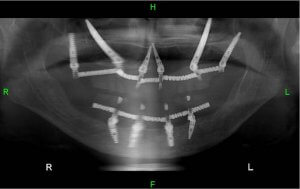

Скуловые импланты, имплантированы в обе стороны верхней челюсти пациента.

Продолжая тему о случаях, в которых челюстная кость пациента недостаточно плотная для крепления имплантов, врач прикрепляет зубной имплант к костям,

которые находятся над челюстью, в щеках, они также известны как скулы.

Для имплантации по данной методике зубной врач использует скуловые импланты.

Эти импланты длиннее стандартных зубных имплантов, проникают дальше челюстной полости, и крепятся к скулам.